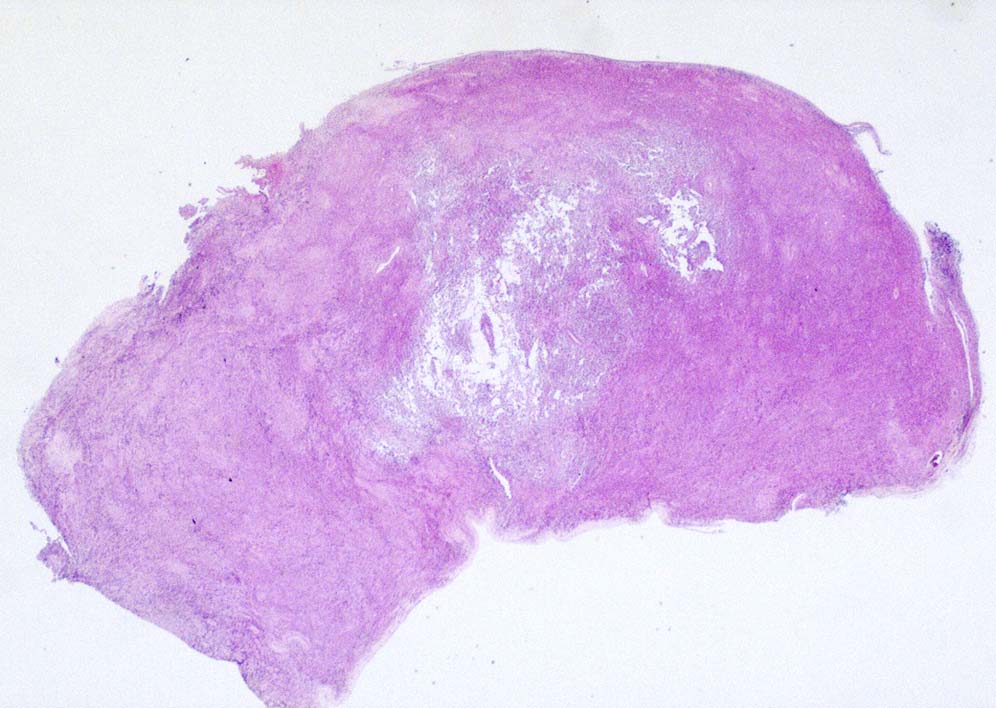

5ヵ月後右主気管支を圧迫しほとんど閉塞する巨大な腫瘍を認めた. 他院で緊急放射線療法および化学療法を行うが効果なし. 腫瘍切除+右肺上葉切除をおこない肉眼的には腫瘍は完全切除できた. 病理診断は非典型的であるが malignant SFT. 当院に再入院, radiation therapyをおこなう. 効果乏しく, 腫瘍は進行し呼吸不全で永眠される.

胸腔鏡下ブラ切除術5ヵ月後, 縦隔腫瘤で再発. 他院で腫瘍切除+右肺上葉切除を施行. 肉眼的には腫瘍は完全に切除できた.

病理診断は, 非典型的所見ながらmalignant solitary fibrous tumorとされた.(剖検時点ではSMARCA4-DTSの疾患概念はなく, 知見も得られていなかった.)